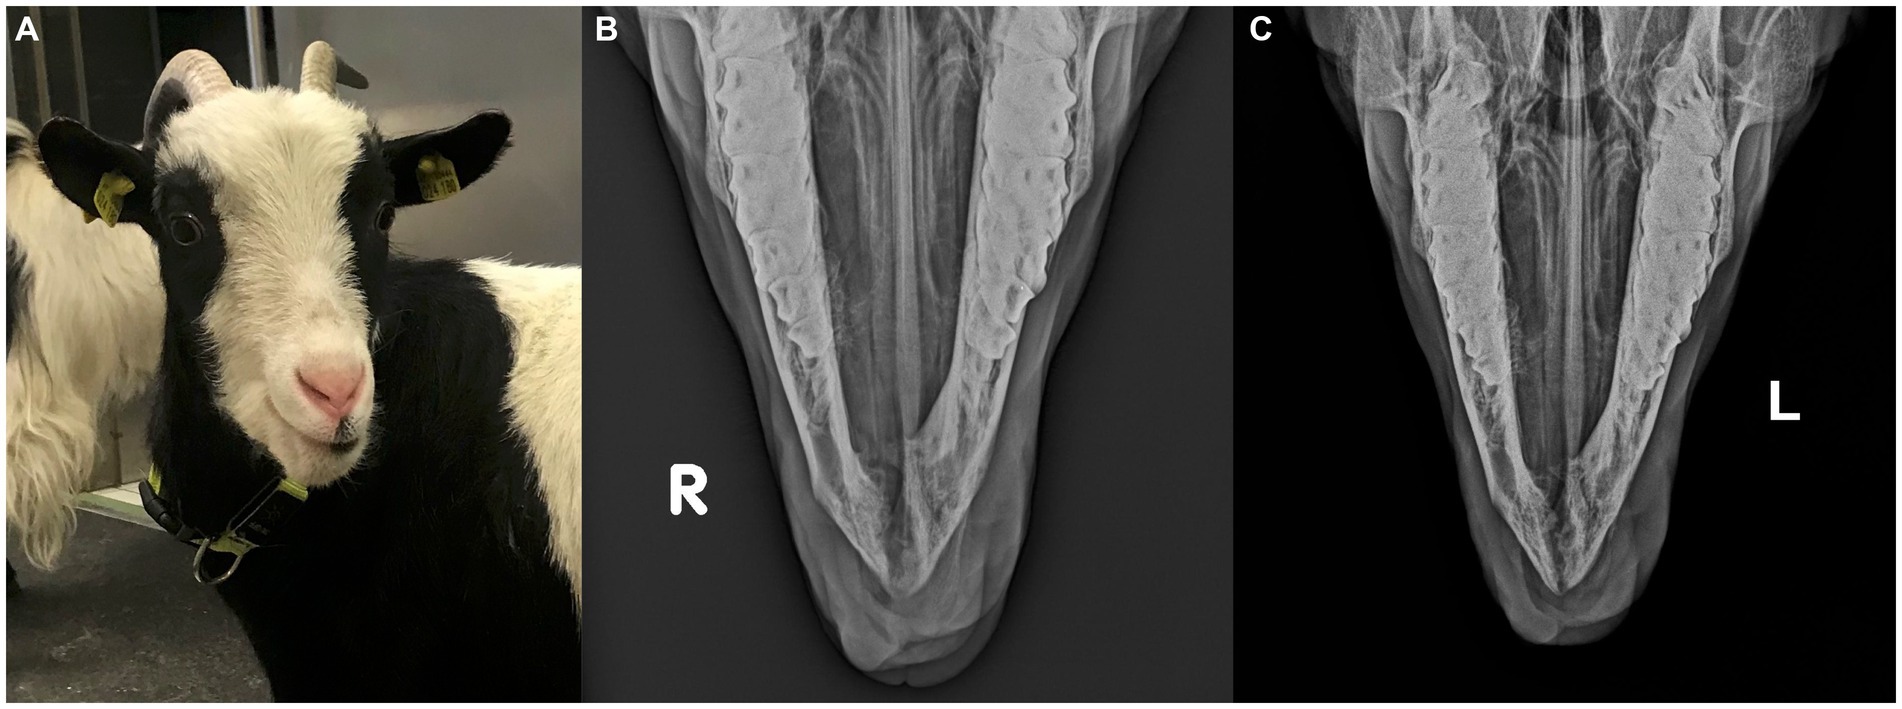

En el momento de la presentación, los parámetros del examen físico estaban dentro de los límites normales y la cabra estaba en buenas condiciones corporales. Una masa firme y no dolorosa de aproximadamente 30 mm × 25 mm × 30 mm desplazó los dientes incisivos mandibulares izquierdos, siendo el tercer diente incisivo mandibular izquierdo muy móvil. La masa estaba cubierta en su mayor parte por mucosa oral parcialmente ulcerada y firmemente adherida a la mandíbula (Figura 1A). Un aspirado con aguja fina, tomado después de anestesia local, no fue diagnóstico.

www.frontiersin.orgFigura 1(A) Imagen preoperatoria de una cabra pigmea de 2 años con un tumor óseo de células gigantes que involucra la mandíbula rostral. (B) Radiografías frontomandibulares y (C) laterales de la mandíbula rostral de una cabra con un tumor óseo de células gigantes. Se muestra una masa expansiva y multicavitada, principalmente dentro de la corteza mandibular, con principalmente signos de lisis que involucran la sínfisis mandibular. Los dientes incisivos mandibulares izquierdos están desplazados y parcialmente cubiertos por tejido blando que sobresale.

Las radiografías mostraron una masa expansiva y multicavitada dentro de la corteza mandibular rostral, incluida la sínfisis, que se extendía caudalmente aproximadamente a la mitad de ambos dientes premolares mandibulares. Observaron signos marcados de reabsorción ósea alveolar con desplazamiento lateral de los dientes incisivos mandibulares izquierdos, que estaban parcialmente cubiertos por tejido blando protuberante (Figuras 1B,C).